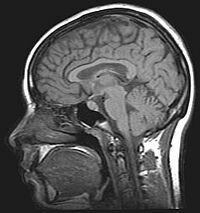

• Resonancia Magnética nuclear

Resonancia Magnética nuclear

Félix Bloch y Edward Purcell descubren la resonancia magnética nuclear.